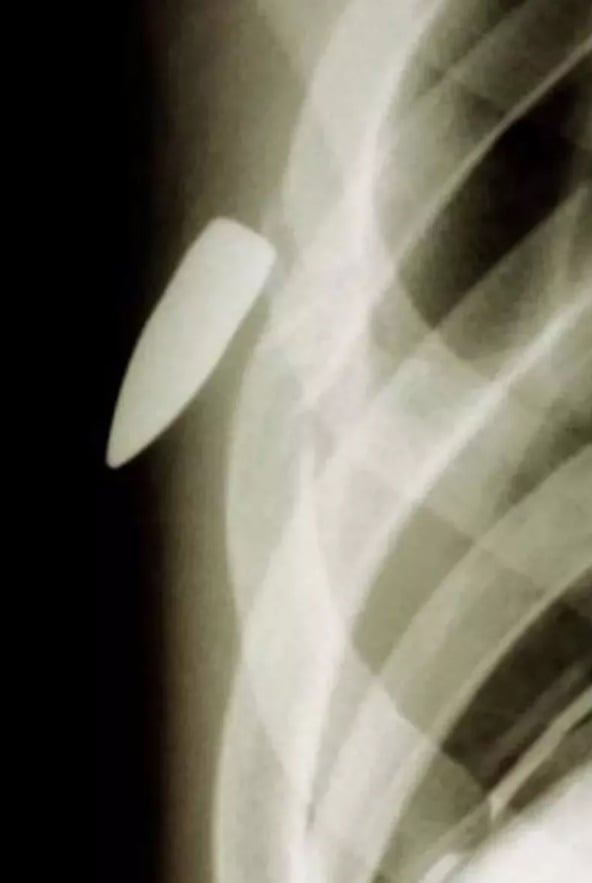

Göğüs kafesinde kurşun olan bir hasta...